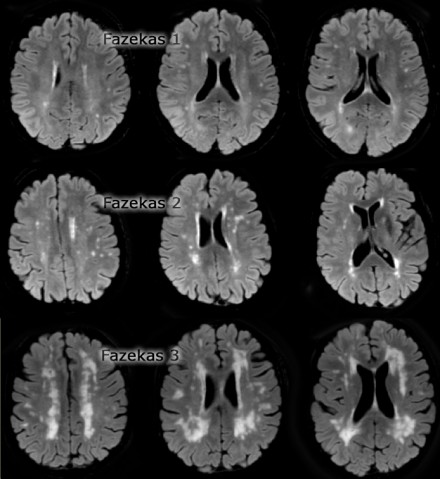

La scala di Fazekas (Fig.3), qualitativa, è la più usata per determinare la dimensione delle lesioni nella sostanza bianca nella IRM, e la sua classificazione è la seguente:

– grado 0: assenza di lesioni;

– grado 1: esistenza di lesioni sotto forma di focolai ischemici;

– grado 2: inizio di confluenza dellle lesioni;

– grado 3: diffusione delle lesioni, che comprende intere regioni.